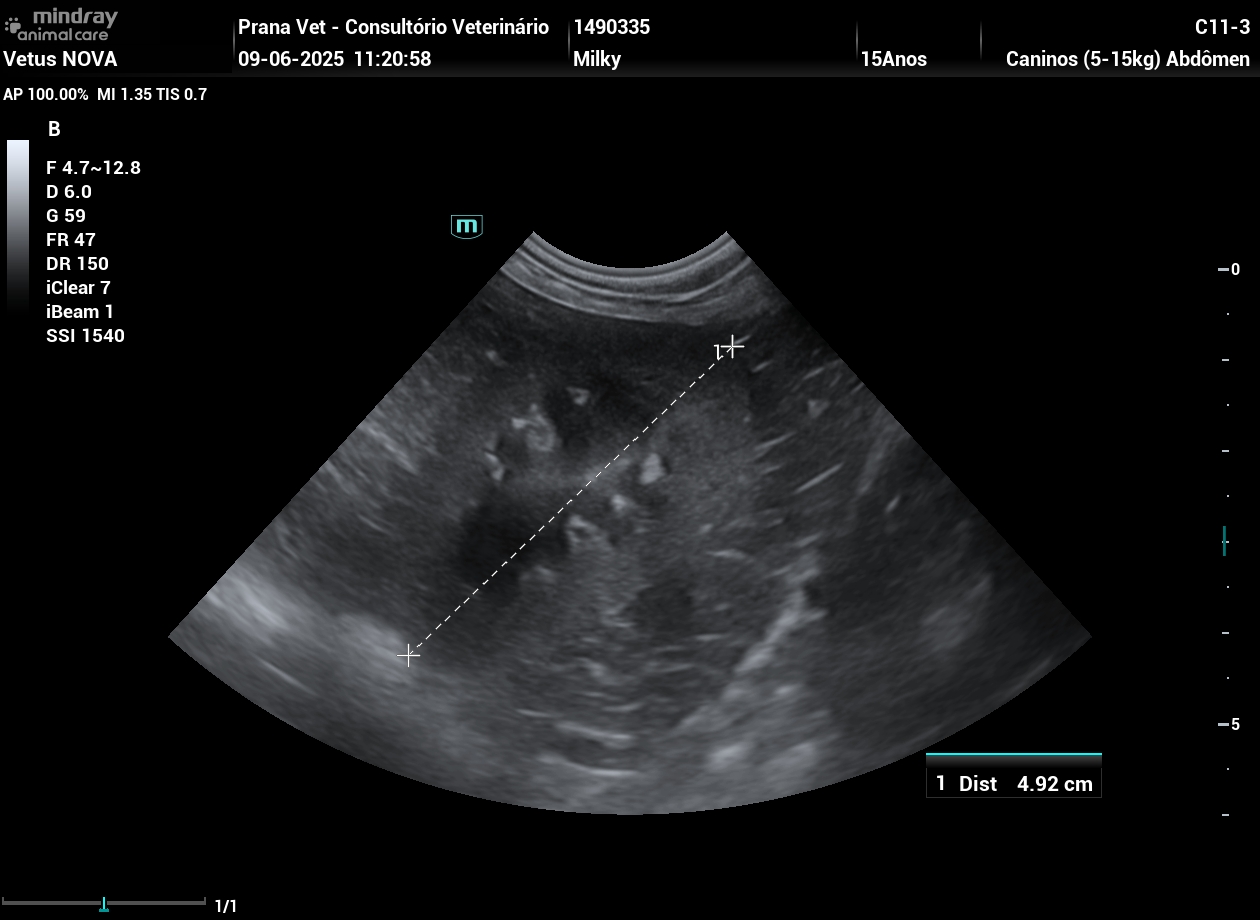

Trabalhamos com o sistema Mindray Vetus Nova, um ecógrafo moderno desenvolvido especificamente para medicina veterinária.

✔ Imagem de alta resolução

✔ Melhor definição de tecidos moles

✔ Avaliação vascular com Doppler

✔ Maior sensibilidade para alterações subtis

✔ Exames mais rápidos e precisos